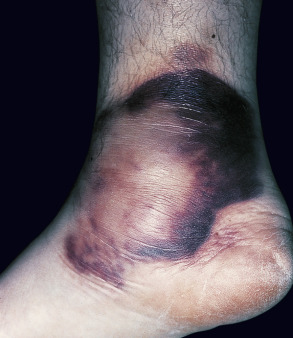

Erythema induratum is characterized by tender, erythematous to violaceous nodules and plaques that most often develop on the lower legs, especially the calves . Lesions have also been reported on the feet, thighs, buttocks and arms . An annular arrangement of nodules has been described in M. tuberculosis -related cases . Ulceration can occur ( Fig. 100.7 ). Lesions are persistent, tend to heal with scarring, and are prone to recurrence . In erythema induratum associated with M. tuberculosis , there may be clinical and radiographic evidence for active tuberculosis, positive skin tests to PPD, or a positive interferon-gamma release assay such as the QuantiFERON ® -TB Gold In-Tube test . In addition, other tuberculids, e.g. papulonecrotic, may be present. Clinical differences between tuberculous and non-tuberculous cases are minor.